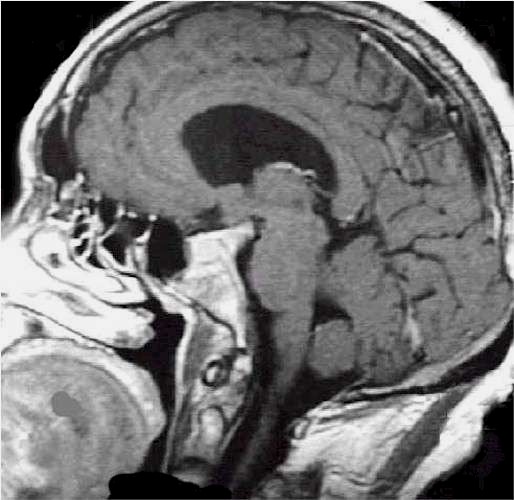

La neuronavigazione comprende sistemi computerizzati avanzati che consentono al chirurgo di conoscere in ogni momento l’esatta posizione dei propri strumenti durante l’intervento chirurgico, permettendo oggi di raggiungere praticamente qualsiasi sede intracranica mediante approcci spesso innovativi e meno invasivi.

Questi sistemi svolgono a tutti gli effetti anche una funzione stereotassica, poiché consentono di localizzare un bersaglio intracranico all’interno di un sistema di coordinate tridimensionali derivato dalle immagini di Risonanza Magnetica o Tomografia Computerizzata, con un’elevata accuratezza spaziale. In tal senso, la neuronavigazione può essere considerata una

stereotassia frameless, che non richiede l’applicazione di un casco stereotassico rigido, garantendo maggiore flessibilità e comfort per il paziente.

Il procedimento ha inizio con l’esecuzione di una Risonanza Magnetica (RM) o di una Tomografia Computerizzata (TC) del paziente, effettuate mediante protocolli di acquisizione dedicati.

Al momento dell’intervento chirurgico, il capo del paziente viene registrato nello spazio tridimensionale del computer tramite un sistema di localizzazione, generalmente ottico a infrarossi, che riconosce specifici punti di repere applicati al capo o al sistema di fissaggio.

Il computer provvede quindi a sovrapporre l’anatomia reale del paziente alle immagini RM o TC precedentemente acquisite. Durante l’intervento, il chirurgo utilizza strumenti chirurgici dotati di marker che vengono continuamente rilevati dallo stesso sistema ottico a infrarossi; in questo modo il neuronavigatore è in grado di indicare in tempo reale, sulle immagini RM o TC, l’esatta posizione degli strumenti all’interno del campo operatorio.

Grazie a questa tecnologia, l’intervento viene accuratamente pianificato alla consolle del computer, anche nei giorni precedenti l’atto chirurgico, consentendo di valutare in modo approfondito il percorso di accesso più sicuro e riducendo significativamente il rischio di dover effettuare scelte intraoperatorie non sufficientemente ponderate.

Per raggiungere una determinata sede, anche se profonda o localizzata in aree critiche, è possibile adottare traiettorie talvolta più lunghe ma che attraversano regioni cerebrali a minore rischio funzionale per il paziente. In questo modo sono venuti meno molti dei limiti legati alla difficoltà di accesso anatomico (lesioni profonde, sedi eloquenti), che in passato spesso precludevano un trattamento chirurgico.